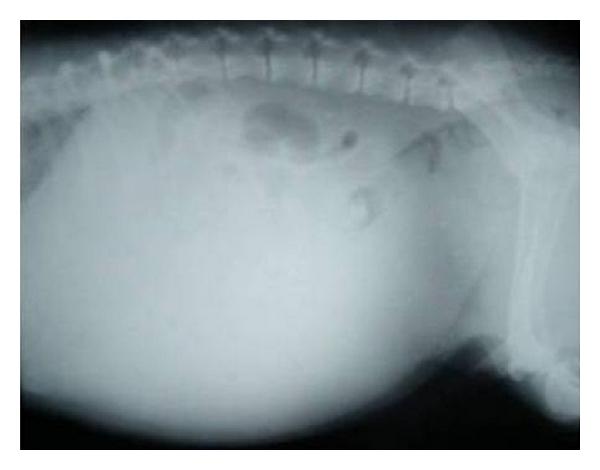

Hepatic disease is often treatable and has a predictable prognosis when a definitive diagnosis is made. The aim of clinicopathological evaluation of hepatobiliary affections is to identify and characterize hepatic damage and dysfunction, identify possible primary causes of secondary liver disease, differentiate causes of icterus, evaluate potential anaesthetic risks, assess prognosis and response to xenobiotics, and monitor response to therapy. This paper describes the different diagnostic methods and imaging techniques employed in diagnosis of hepatobiliary affections in dogs. Besides reviewing the significant clinical manifestations and imaging structural abnormalities in diagnostic approach to different hepatic affections, it also depicts radiographic, ultrasonographic, and wherever applicable, the laparoscopic characterization of different hepatic affections and target lesions encountered in clinical cases presented in the Teaching Veterinary Clinical Complex, COVAS, Palampur in the year 2007-2008.

肝病通常是可治疗的,一旦做出明确诊断,其预后是可预测的。肝胆疾病临床病理评估的目的是识别和描述肝损伤及功能障碍,确定继发性肝病可能的主要病因,鉴别黄疸的病因,评估潜在的麻醉风险,评估预后及对外源化学物质的反应,并监测治疗反应。本文描述了用于诊断犬肝胆疾病的不同诊断方法和成像技术。除了回顾不同肝病诊断方法中的重要临床表现和成像结构异常外,还描述了2007 - 2008年在帕兰普尔兽医临床综合教学中心(COVAS)出现的临床病例中不同肝病及目标病变的放射学、超声学特征,以及在适用情况下的腹腔镜特征。